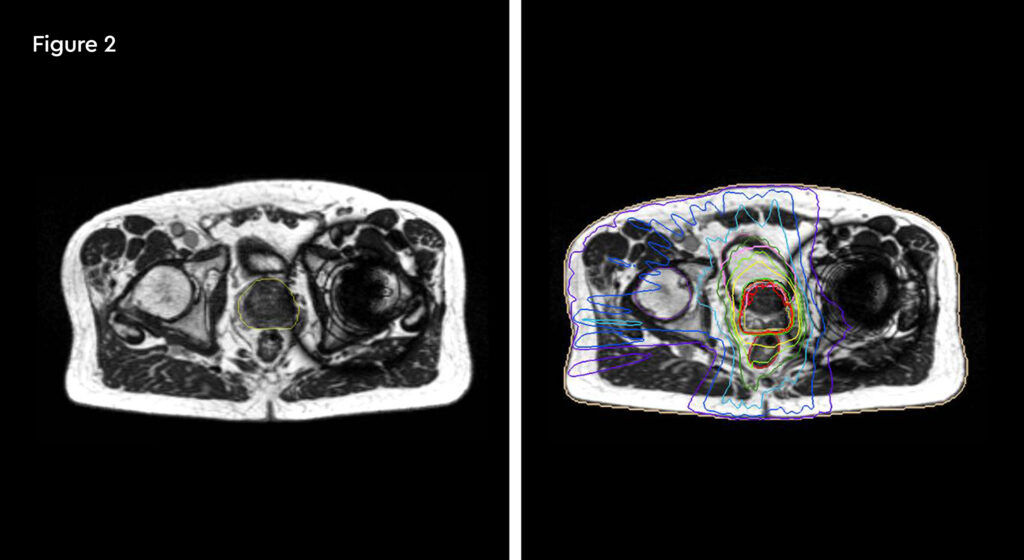

At each session, daily adaptation was performed to account for changes in the position of the prostate and for variable bladder and bowel filling. Figure 1 and figure 2 illustrate the typical differences seen between the original planning MRIdian scan and that seen on the day of treatment due to day-to-day organ movement. Figure 3 and figure 4 illustrate how these movements were accommodated with the on-table plan adaptation.

Fig 1: Original planning MRIdian scan

Fig 2: MRIdian scan at fraction 3, prostate position changed due to larger rectal diameter secondary to gas and smaller bladder

Fig 3: Prostate SABR delivery plan. Prostate volume covered by 95% isodose (green line, red arrow). Tight conformality at rectal/prostate boundary (white arrow), and rapid drop off of high dose (50% isodose, green line, green arrow) to optimise dose delivery to the prostate and limit dose to the rectum, reducing the risk of toxicity

Fig 4: Fraction 3, adapted plan, optimised for anatomy of the day. Prostate volume covered by 95% isodose (green line, red arrow). Tight conformality at rectal/prostate boundary (white arrow), and rapid drop off of high dose (50% isodose, green line, green arrow) to optimise dose delivery to the prostate and limit dose to the rectum, reducing the risk of toxicity